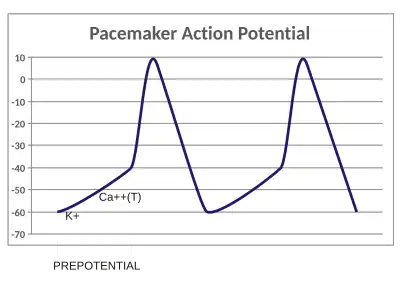

Action potential

In physiology, an action potential is the brief (about one-thousandth of a second) reversal of electric polarization of the membrane of a excited cells such as nerve cell (neuron), muscle cell, endocrine cell and so on.[30]. In neurons, an action potential happens when a neuron sends information down an axon, away from the cell body. In other types of cells, they activate intracellular processes. In muscle cells, for example, an action potential produces the contraction required for all movement. In beta cells of the pancreas, they induce release of insulin.[31] Action potentials in neurons are also known as "nerve impulses" or "spikes", and the temporal sequence of action potentials generated by a neuron is called its "spike train". A neuron that emits an action potential is often said to "fire"[32].

Action potentials are generated by specific voltage-gated ion channels embedded in a cell's plasma membrane.[33] These channels are shut when the membrane potential is near the resting potential of the cell, but stimulation of the cell by neurotransmitters or by sensory receptor cells partially opens channel-shaped protein molecules in the membrane. Sodium diffuses into the cell, shifting that part of the membrane toward a less-negative polarization. If this local potential reaches a critical state called the threshold potential (measuring about −60 mV), sodium channels open completely. Sodium floods inside the cell quickly depolarizes to an action potential of about +55 mV. The declining phase of the action potential is from the closing of sodium channels and the opening of potassium channels, which let a charge about equal to the stage which the cell leaves in the form of potassium ions. Therefore, protein transport molecules pump sodium ions out of the cell and potassium ions in. This restores the original ion concentrations and the membrane is ready for a new action potential.